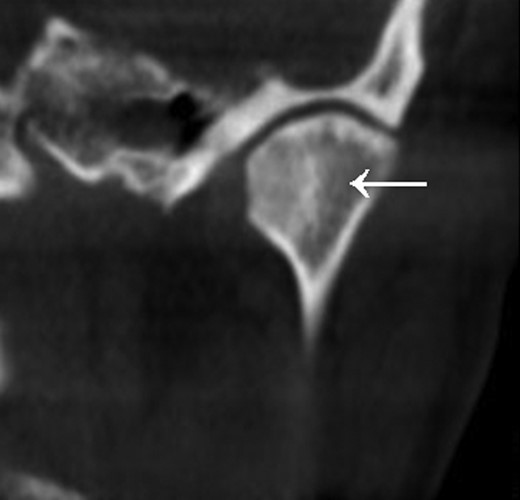

Approximately 4 months later symptoms returned. A computed tomography (CT) scan of the head was ordered by the oncologist. An osteolytic lesion and partial sclerosis of the right condylar head and neck were found, as well as effusion in the right TMJ (Fig. 1). The signs were interpreted as arthritis of the TMJ.

CT scan of the head (coronal section), arrow indicates osteolysis of the right condylar head.